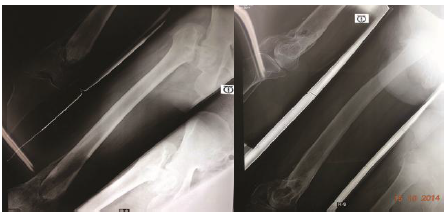

Case illustrations: (Figure 7-13).